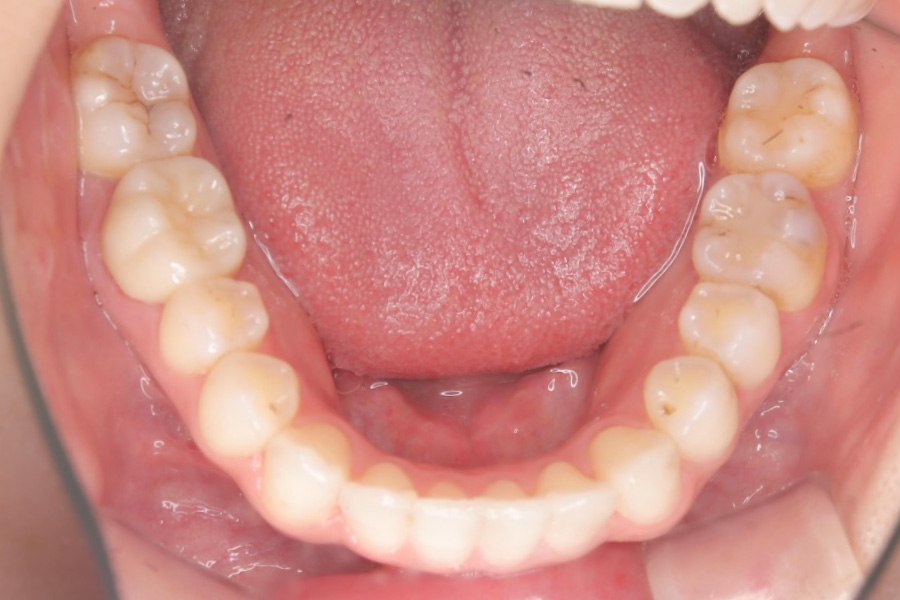

【30代女性】八重歯を

インビザライン矯正で治療したケース

治療後

主訴 八重歯

期間 2年半

費用 220,000円〜660,000円

(デンタルローン 3,100〜6,600円/月)

治療内容 インビザライン矯正

非抜歯